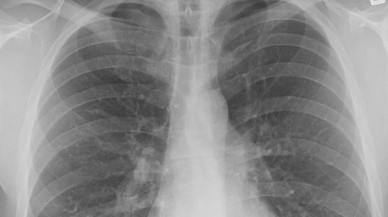

Akciğer Kanseri Haberleri

Son Dakika Akciğer Kanseri Haberleri

Bu sayfada güncel gelişmeleri takip edenler için Akciğer Kanseri ile ilgili en son gelişmeler ve son dakika Akciğer Kanseri haberleri sunulmaktadır. Akciğer Kanseri videoları, Akciğer Kanseri fotoğrafları ve Akciğer Kanseri haberleri